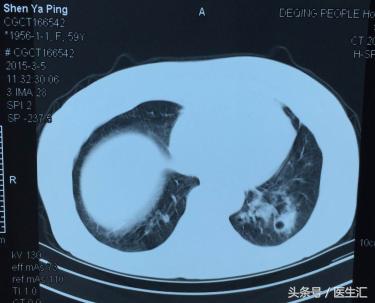

3月5日CT

患者1月前受凉下出现咳嗽咳痰,痰不易咳出,无畏寒发热,无胸闷气急,无胸痛心悸等不适。自服相关药物后咳嗽略有好转10天前患者咳嗽咳痰加重,痰色白量多,伴发热,最高体温达39℃,无畏寒寒战,伴胸闷气急,遂至当地医院就诊。查血常规+CRP:WBC 1.8*10^9/L,N 25.5%,CRP 3.1mg/L。胸部CT:两下肺感染性病变,左侧明显,左下空洞样改变。药物治疗后,体温降至正常后又上升,常晚间发热,体温在37.5℃-38.5℃之间,建议其转上级医院就诊。遂来我院门诊,复查血常规:WBC3.0*10^9/L,N55.5%,L33.7%,Hb137g/L,PLT123*10^9/L。予可乐必妥片抗感染,百服宁降温,苏黄止咳胶囊镇咳。患者仍有咳嗽咳痰,无畏寒发热,无胸闷气急。